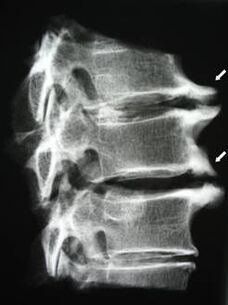

Во почетните фази, остеохондрозата се открива со помош на МНР. Подоцна, патологијата може да се дијагностицира со помош на радиографија. На радиографија на цервикалниот 'рбет, станува забележливо намалување на растојанието помеѓу пршлените, патолошки промени во зглобовите на фасетите и остеофитоза.